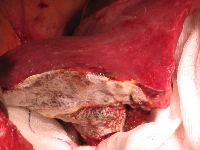

Πρόκειται για γυναίκα ασθενή 47 ετών, η οποία υποβλήθηκε σε κολονοσκόπηση για άτυπα γαστρεντερικά συμπτώματα. Διαπιστώθηκε αδενοκαρκίνωμα σιγμοειδούς με δύο σύγχρονες μεταστατικές εστίες στο δεξιό λοβό του ήπατος (εικόνα 1). Ακολούθησε σιγμοειδεκτομή. Έλαβε 12 κύκλους χημειοθεραπείας με Avastin και FOLFOX. Κατόπιν υποβλήθηκε σε δεξιά ηπατεκτομή (εικόνα 2). Στο παρασκεύασμα φαίνονται οι δύο μεταστατικές εστίες, η μεγαλύτερη εκ των οποίων είναι 4 εκατοστά (εικόνα 3). Ο όγκος του υπολοιπόμενου ήπατος ανήλθε από 39% σε 62%, ένα μήνα μετά την ηπατεκτομή (εικόνα 4). Δεν έλαβε μετεγχειρητική χημειοθεραπεία. Η ασθενής εξακολουθεί να είναι ελεύθερη νόσου.